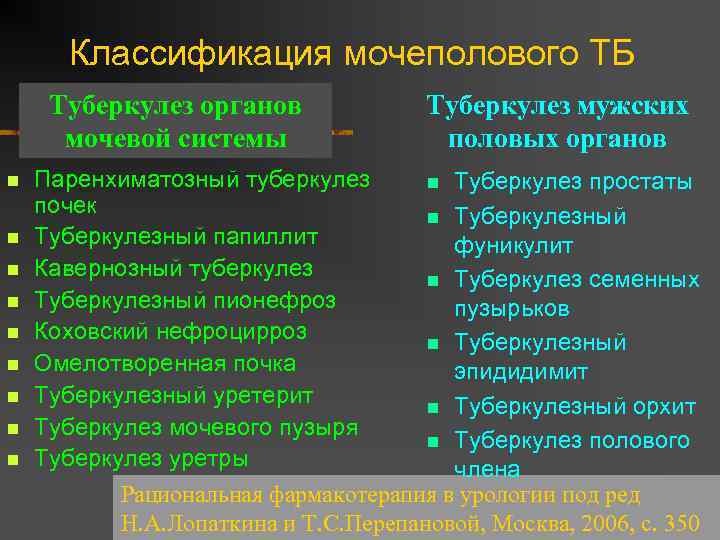

Понимание кавернозного туберкулеза почки

Раздел: Мудрость в деталях